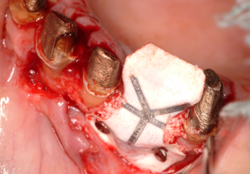

骨移植はインプラント埋入より、高度な技術が必要ですのでなるべくこの処置をしなくて済むように考案されたのがオールオン4などのコンセプトです。しかし、オールオン4ができないくらい骨がたりない場合などには行います。